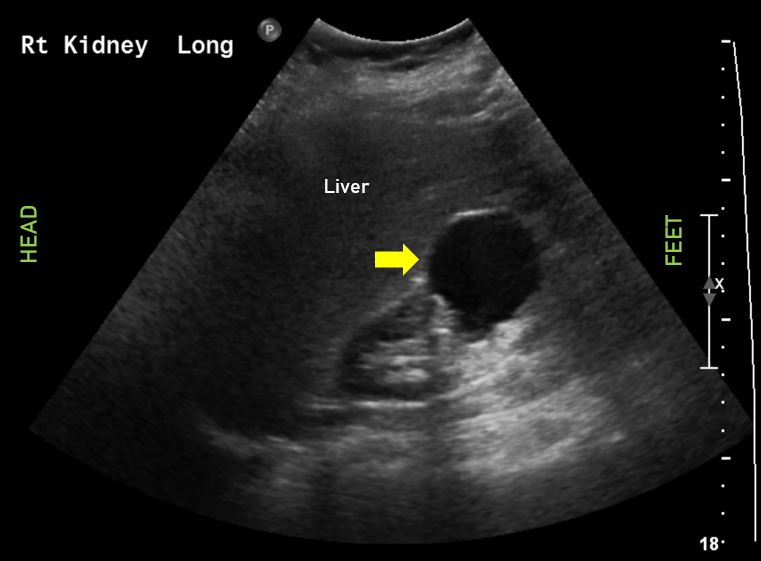

6. kép:

Húgyvezeték kő 1.

Ezen a képen egy követ láthatunk az ureter kezdeti szakaszán (fehér nyíl). Az előtte lévő szakasz valamint a vese medence tágabb.